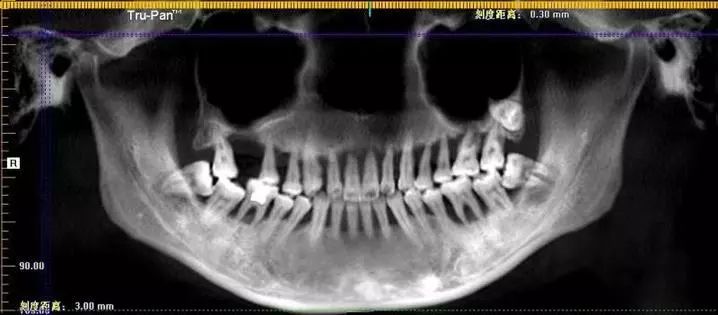

牙片中清晰可见小萌的上口牙已摇摇欲坠

6年时间从轻度到重度牙周炎